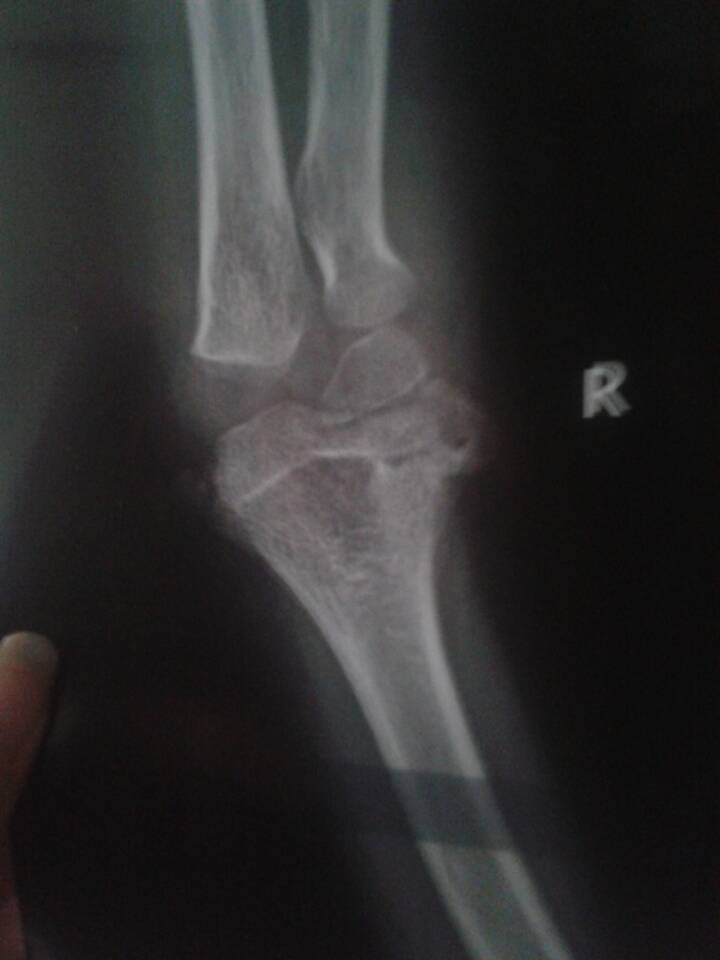

小孩胳膊摔坏了,已经两个月了,再去复查拍了这样的片子,这严重吗?能长好吗? 点击展开 匿名用户 2015-04-17 15:30 满意回答 看局怨图,还是有点骨竖院裂,不过孩子生长,旺盛,一般会痊愈的。 如果复查。还是很迷编禁厉害,吊绑。或者石膏。要用上,防止骨节错位, 出千山_gJ9o 2015-04-17 16:16 宝宝知道提示您:回答为网友贡献,仅供参考。 相关问题 宝宝五岁了胳膊不小心摔着了去医院拍片子没�?可还是疼不能�?怎么回事呀 我怀孕7个月把胳膊给摔了,能拍片子吗?X射线 两岁小孩大腿,和胳膊长像痱子一样东西,痒痒的,都抓破了